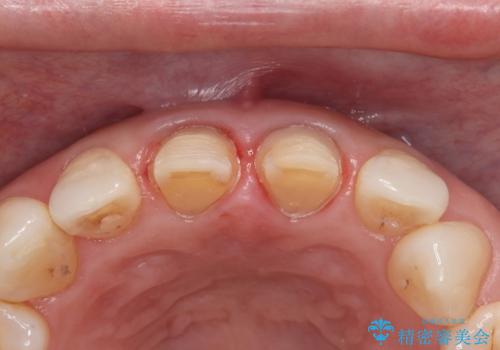

- 前歯の色が年々変わっていき、見た目が気になるので綺麗な歯にしたいと思い当院へ来院されました。

保険ですでに治療がされており、経年劣化が見られ内部にはう蝕もあったため除去し、オールセラミッククラウンにて治療いたしました。